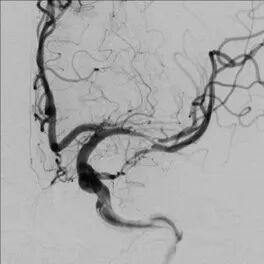

全脑及病变处不同体位造影:狭窄处成形好,未残余明显狭窄,左大脑中动脉主干及各分支显影好。

导丝怎么扩【载药时代 球扩天下】NOVA DES®颅内药物球扩支架在大脑中动脉重度狭窄中的应用——济南市第四人民医院使用体会一例!_https://www.jmylbn.com_新闻资讯_第13张

导丝怎么扩【载药时代 球扩天下】NOVA DES®颅内药物球扩支架在大脑中动脉重度狭窄中的应用——济南市第四人民医院使用体会一例!_https://www.jmylbn.com_新闻资讯_第14张